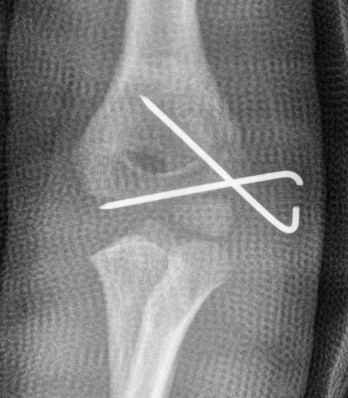

1. Closed reduction and percutaneous K wires

Closed reduction and percutaneous K wires

Indications

- residual displacement < 2 mm

- no rotation

- confirm joint surface anatomically reduced (arthrogram)

Technique

- reduce by extension and varus

- pronation uses flexor mass to pull lateral condyle forward

- percutaneous K wire

- one K wire parallel to joint surface across fracture into trochlea

- one K wire at 45 degrees to first engaging medial metaphysis

- bury K wires as need to be in for 6 weeks